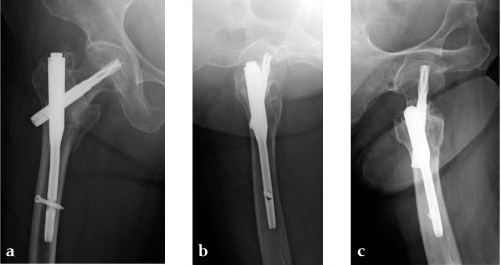

To help cope with the differences described above, an Asian version of the existing Proximal Femoral Nail Antirotation (PFNA) was developed and introduced into the market. The PFNA Asia (also known as PFNA II) (Fig 1) has a better fit to the smaller trochanteric area and narrower intramedullary canal of the Asian population. It features a lateral flat surface which makes insertion easier and lowers the pressure on the lateral cortex. The bend has been reduced to 5° versus 6° compared to the PFNA. The proximal diameter has been reduced to 16.5 mm (versus 17.0 mm). Furthermore, the spiral blade diameter has been reduced to 10.3 mm.

She was operated on the next day and fixed with a PFNA Asia (size: extra small, angle 130 degrees, distal diameter: 9 mm, blade length 100 mm) (Fig 6a). Good reduction and stable fixation were obtained. Full weight-bearing gait was allowed on the second postoperative day. There was an uneventful postoperative course, and good union was obtained at three months after surgery (Fig 6b).